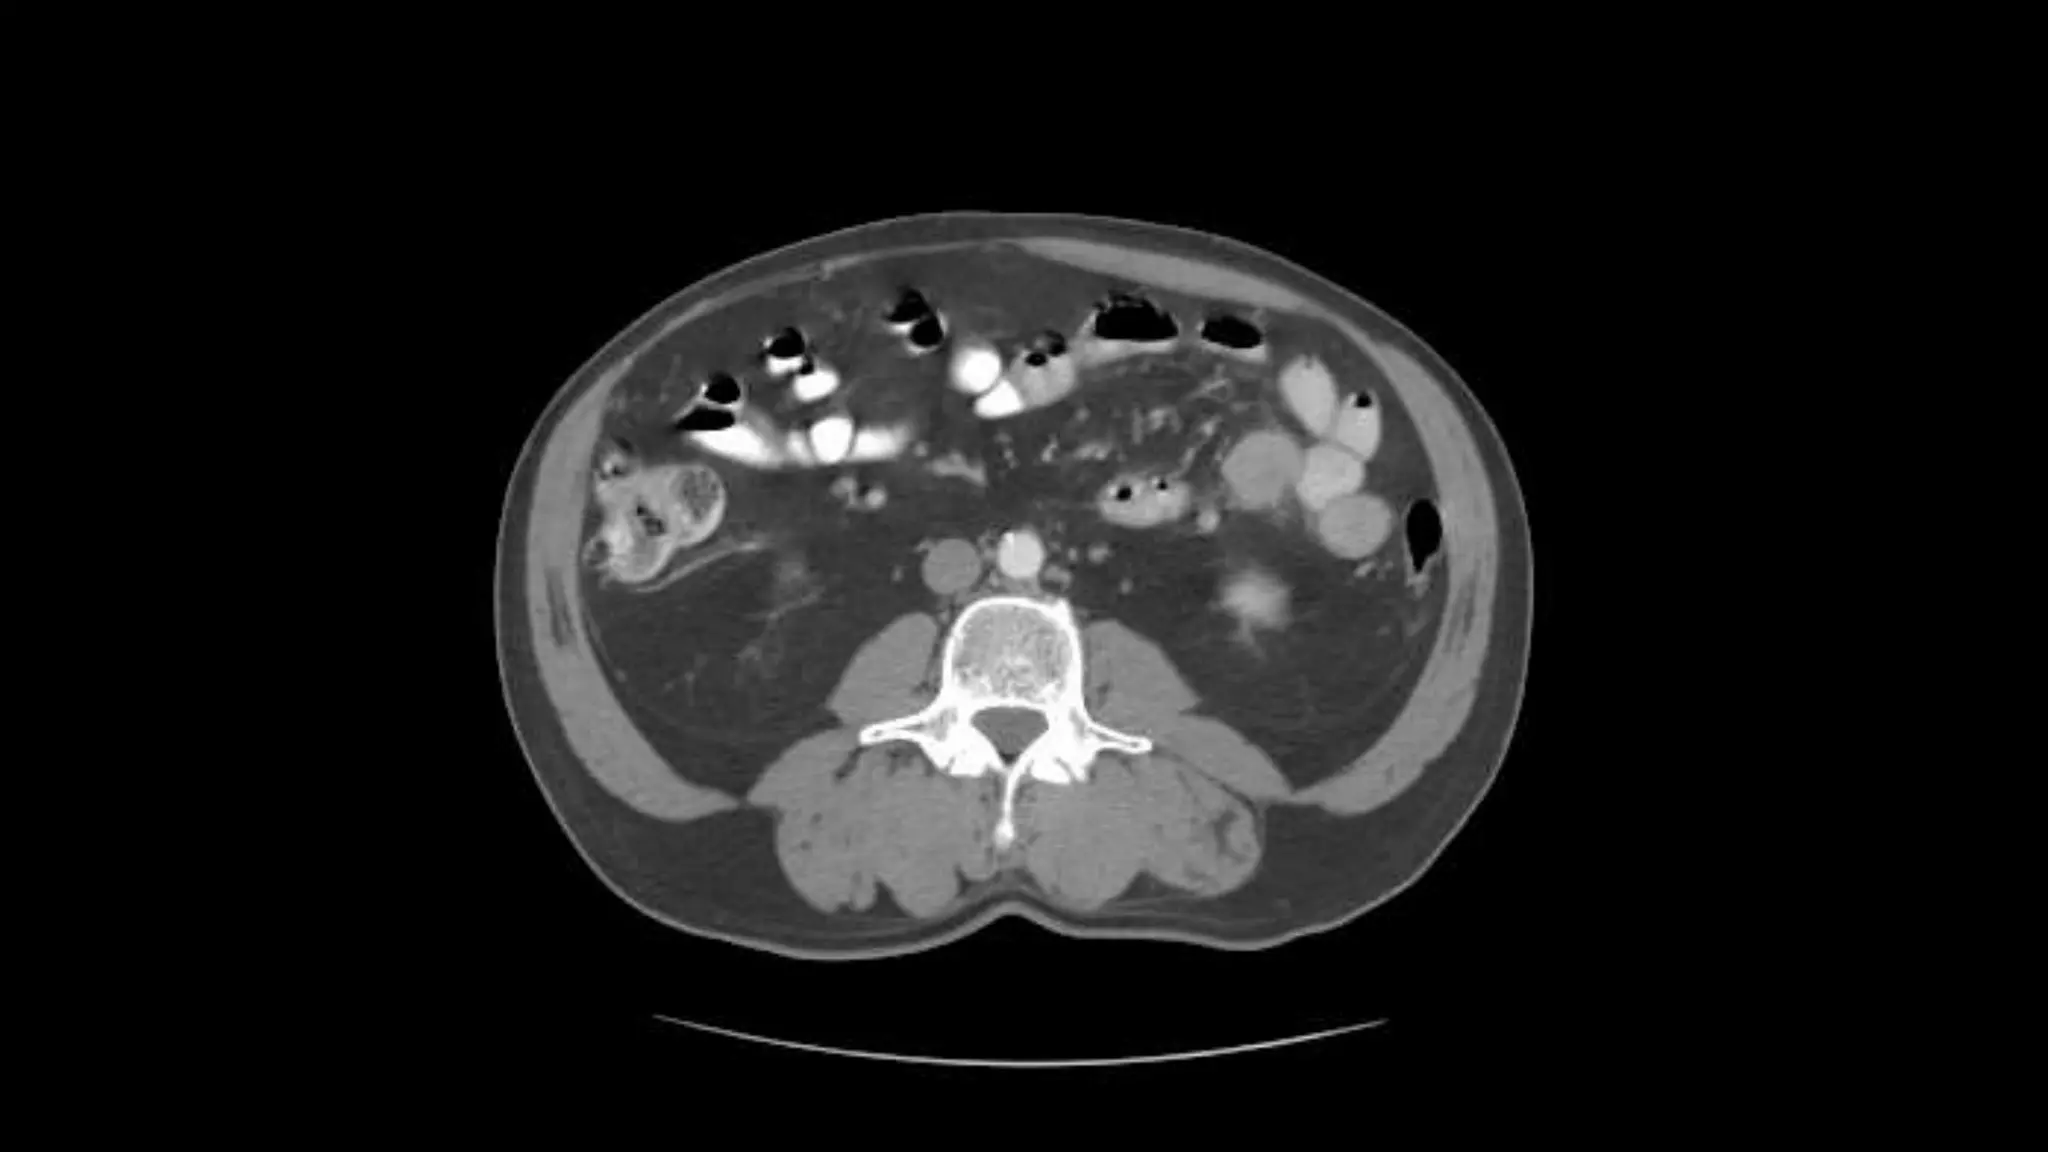

Superior Mesenteric Vein – follow it up as it joins the Splenic

Vein to form the Portal Vein

Transverse Colon Small Bowell

Note inferior mesenteric artery emerging from aorta

Inferior mesenteric vein extends cephalad to join smv.

Aorta bifurcates into common illiac arteries

Appendix is noted coiling in Rt. Lower quadrant

Note air in lumen on adjacent scans

Psoas

muscles